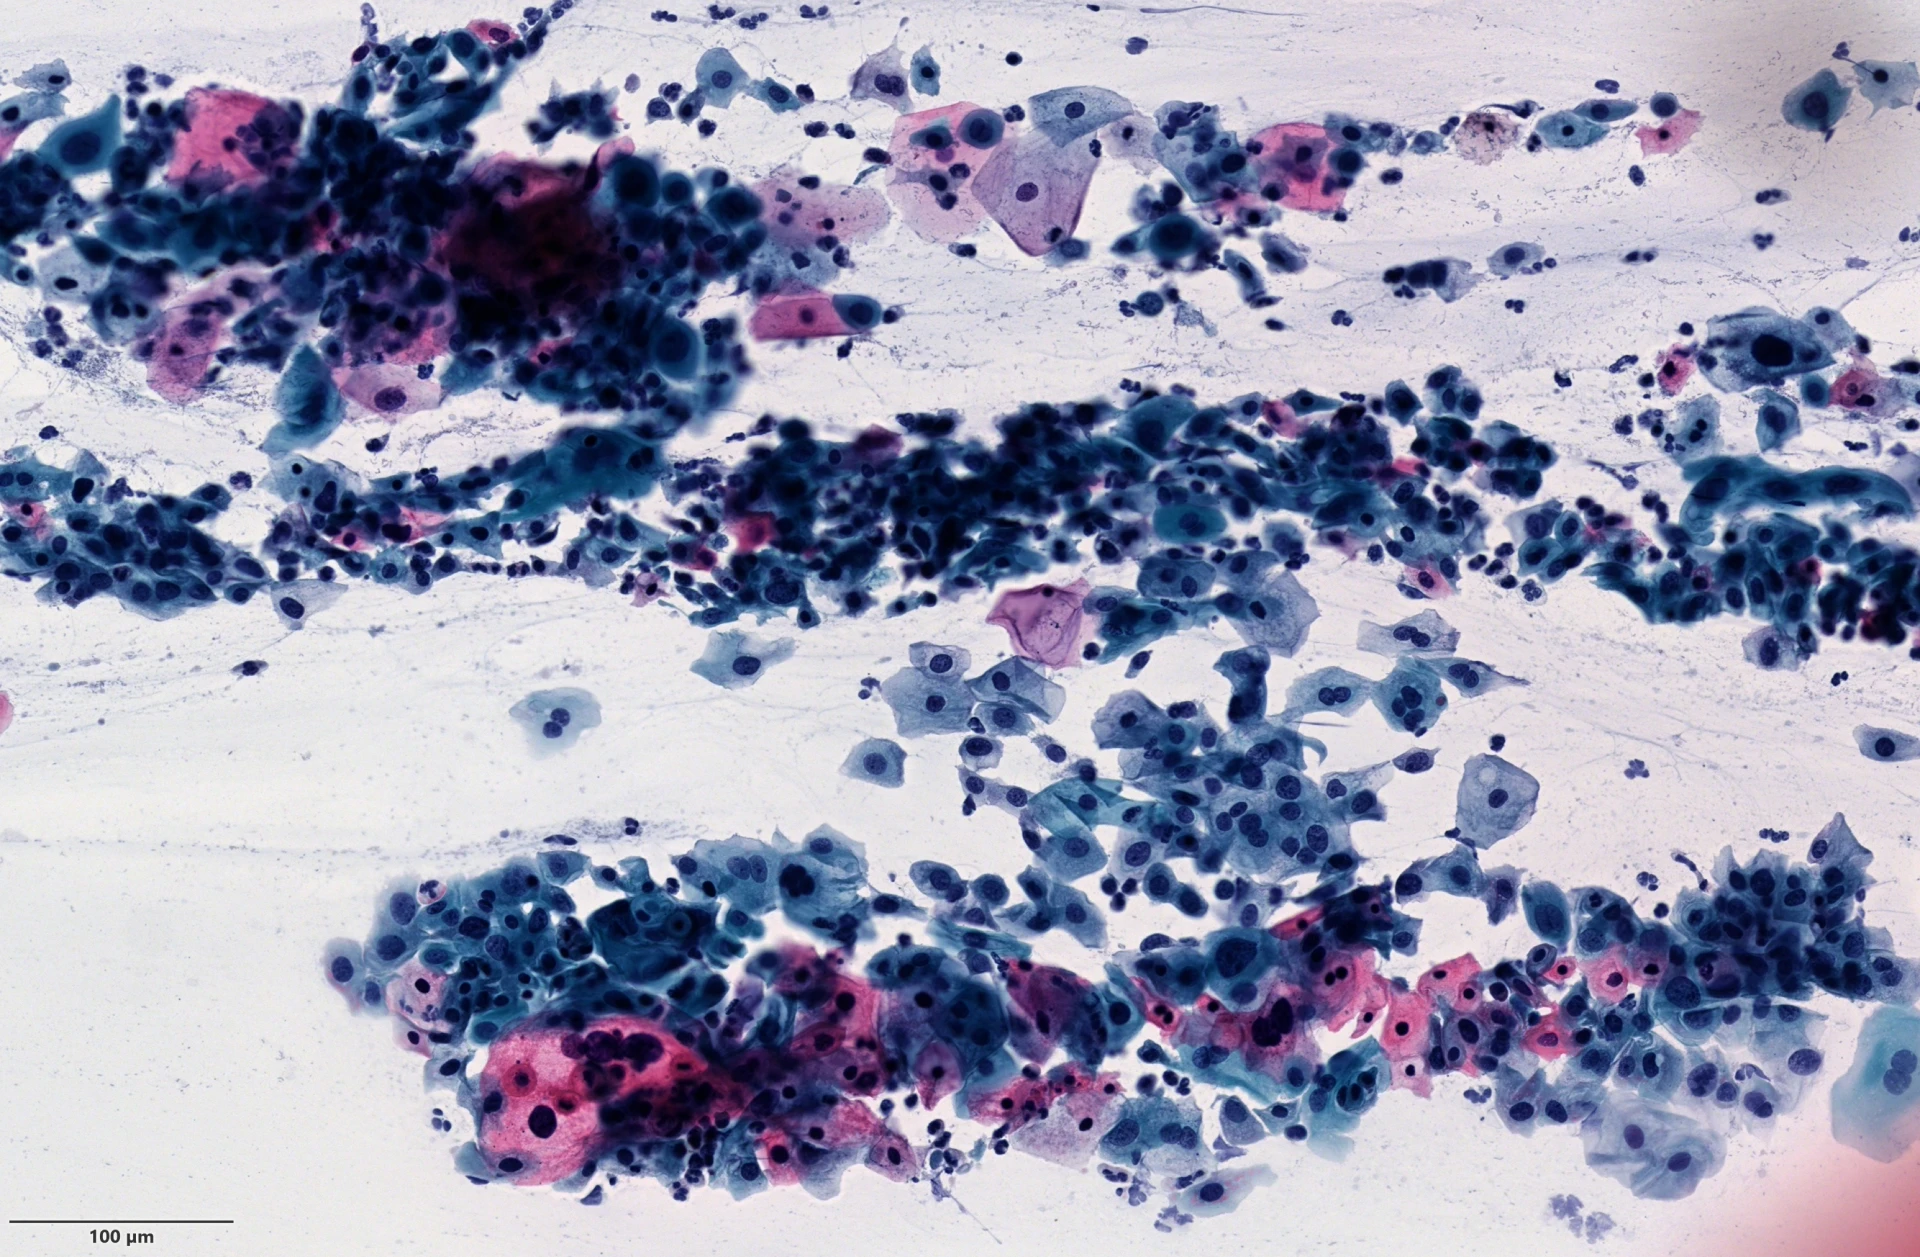

Die zytologische Untersuchung von Abstrichpräparaten, Zytozentrifugaten aus Körperflüssigkeiten und Feinnadelpunktionen mit der Möglichkeit zur immunzytologischen Analyse erlaubt eine diagnostische Einschätzung an nur geringen Mengen von Zellen oder kleinen Zellverbänden.

Bei Feinnadelaspiraten für komplexe zytologische Fragestellungen, insbesondere in der Tumordiagnostik kommt die Bearbeitung im Zellblockverfahren (sog. Zellpellets) zum Tragen.

Große Bedeutung hat die Zytologie neben ihrem Einsatz in der Diagnostik in der Krebsvorsorge (vor allem in der Frauenheilkunde) sowie in der Tumornachsorge. Die Vorteile der Zytologie liegen in der für die Patienten häufig weniger belastenden Materialgewinnung (Abstriche, Urin, andere Körperflüssigkeiten) sowie dem im Vergleich zur Histologie deutlich geringeren technischen Aufwand.